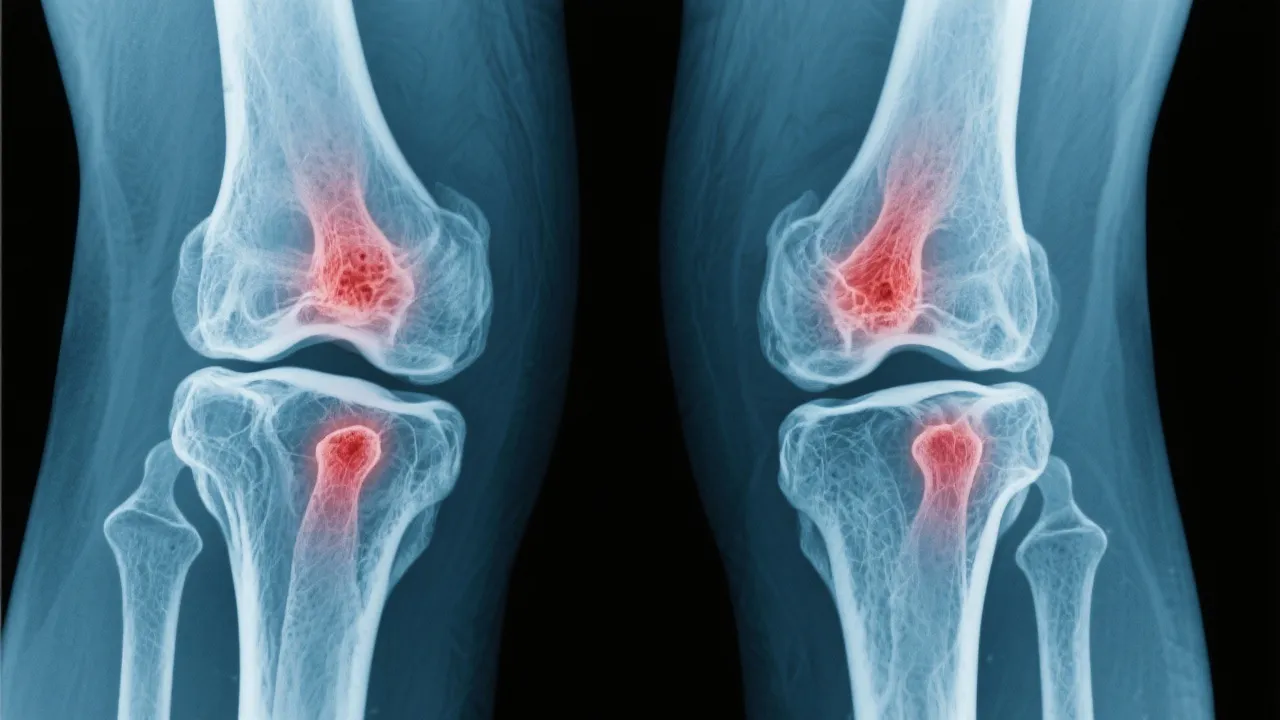

Addressing arthritis joint pain involves a detailed understanding of various treatment options designed to alleviate discomfort and improve quality of life. This article navigates through the landscape of arthritis treatment, exploring medical insights and evidence-based approaches to manage joint pain effectively. Examining arthritis, a prevalent condition impacting many, we dissect various methodologies employed to counteract the debilitating effects of joint inflammation.

Understanding Arthritis and Its Impact

Arthritis, a term encompassing over 100 different conditions, primarily involves inflammation of the joints. This condition is characterized by pain, stiffness, and swelling, which can significantly impair daily activities and quality of life. As individuals age, the prevalence of arthritis increases, making it a common concern among the elderly, though it can affect younger demographics as well. Arthritis can manifest in various forms and can impact not only the joints but also other organs in the body, causing systemic symptoms and complications. It is crucial to understand the underlying pathophysiology of arthritis to better appreciate how it affects individuals’ daily lives and the complexities involved in its management.